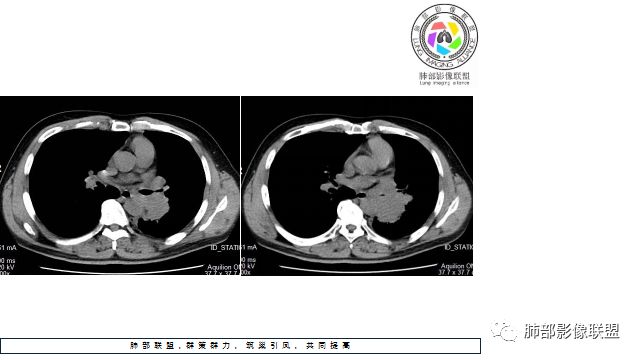

1.左下肺门区巨大肿块,支气管显示不清,轻度阻塞性炎症,没有明显肺不张,提示管腔受压狭窄可能性大于堵塞,这较少见于鳞癌。

2.病灶边缘光滑,未见明显分叶、毛刺,未见明显强化,这符合腺癌影像学特点,却符合神经内分泌癌表现。

3.病灶内密度均匀,轻到中度均匀强化,大病灶未见明显液化坏死区及空洞,不符合鳞癌而符合小细胞肺癌特点。

4.病灶内有肺动脉走形,血管局部受压,未见破坏,病灶乏血供,呈血管包埋或血管造影征;侵袭性力强及破坏力弱、血管漂浮都符合SCLC,所以鳞癌的可能性也不大。

5.左肺门块影或淋巴结肿大,竭力挤兑肺门血管结构,呈冰冻肺门;有时候SCLC可以单独呈现冰冻肺门,而没有没有冰冻纵隔。

7.须特别注意的是,肺门区的融合块影,不排除它可能仅仅为转移淋巴结。